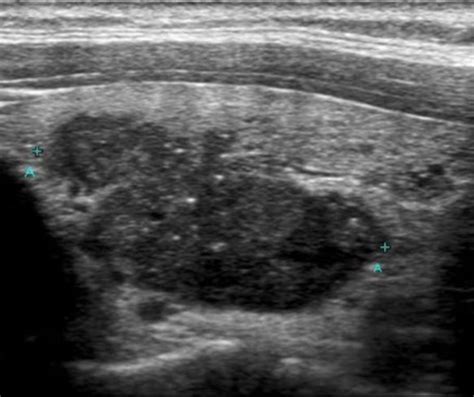

So, what’s the deal with papillary thyroid cancer ? It’s the most common type of thyroid cancer, making up about 80% of all cases. The good news? It’s generally slow-growing and highly treatable, especially when caught early. The thyroid gland, located at the base of your neck, produces hormones that regulate metabolism. In papillary thyroid cancer, abnormal cells start to grow in the thyroid. Most people diagnosed with papillary thyroid cancer have an excellent long-term prognosis after treatment, which typically involves surgery to remove the thyroid (thyroidectomy) and sometimes radioactive iodine therapy to eliminate any remaining cancer cells. However, like any cancer treatment, it can have long-term effects and patients may develop other health issues over time. Common comorbidities associated with thyroid cancer or its treatment can include hypothyroidism (underactive thyroid) if the entire thyroid is removed, which requires lifelong hormone replacement therapy. Patients might also experience fatigue, changes in voice, or issues with calcium levels. Furthermore, survivors are often at a higher risk for developing other metabolic conditions like obesity and diabetes, which is where the interest in GLP-1 agonists really sparks. The long-term surveillance for recurrence is also a crucial part of managing papillary thyroid cancer survivors, and maintaining overall health can significantly impact quality of life. It’s about not just surviving the cancer, but thriving afterward, managing any lingering effects and preventing new health problems. This is precisely why exploring the role of newer medications like GLP-1 agonists in this population is so compelling – could they offer a way to address potential metabolic issues that arise post-treatment?